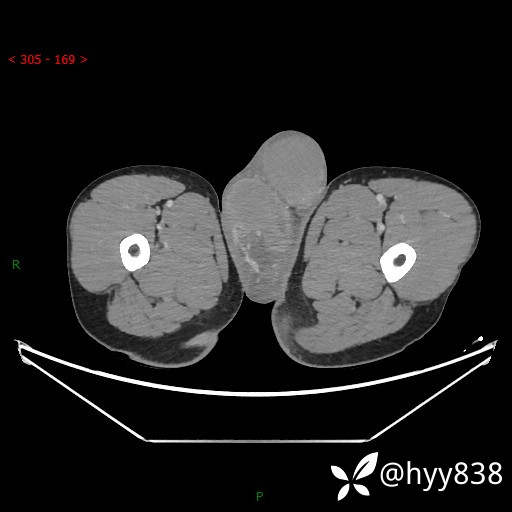

睾丸CT平扫